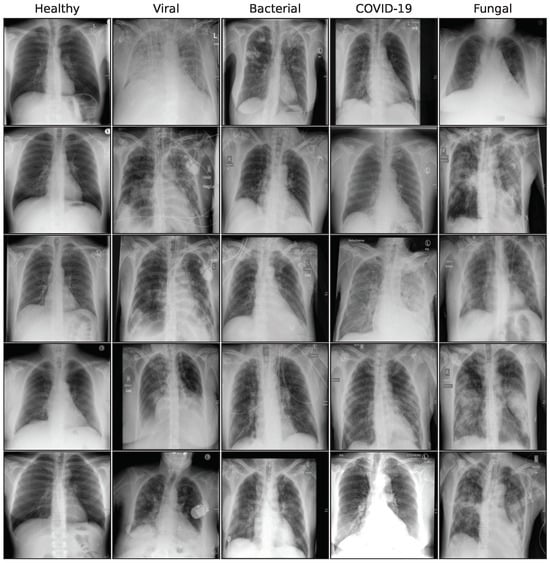

Figure A3. Sample synthetic images from GAN model for all classes.

3.2.1. GAN

Our GAN [15] model is based on the StyleGAN architecture [36] and uses the WGAN-GP-loss and Adam optimizer [37] as in Karras et al. [36]. To ensure a stable training process on our limited study data, differentiable augmentation, as introduced by Zhao et al. [38], is employed. In our internal testing this is a critical step to achieve high quality images from limited data, since the primary source of training instability is the discriminator memorizing the training data. To mitigate this, both real and generated images are augmented with differentiable operations before being fed to the discriminator, facilitating generator training through backpropagation. During training, the resolution increases progressively to stabilize training and achieve higher resolution images. Furthermore, we find that the original StylGAN worked very well with the differentiable augmentation approach. More recent GAN architectures showed increased training complexity with subpar results in our testing. Figure A3 in the Appendix A shows a collection of synthetic images for the GAN model.